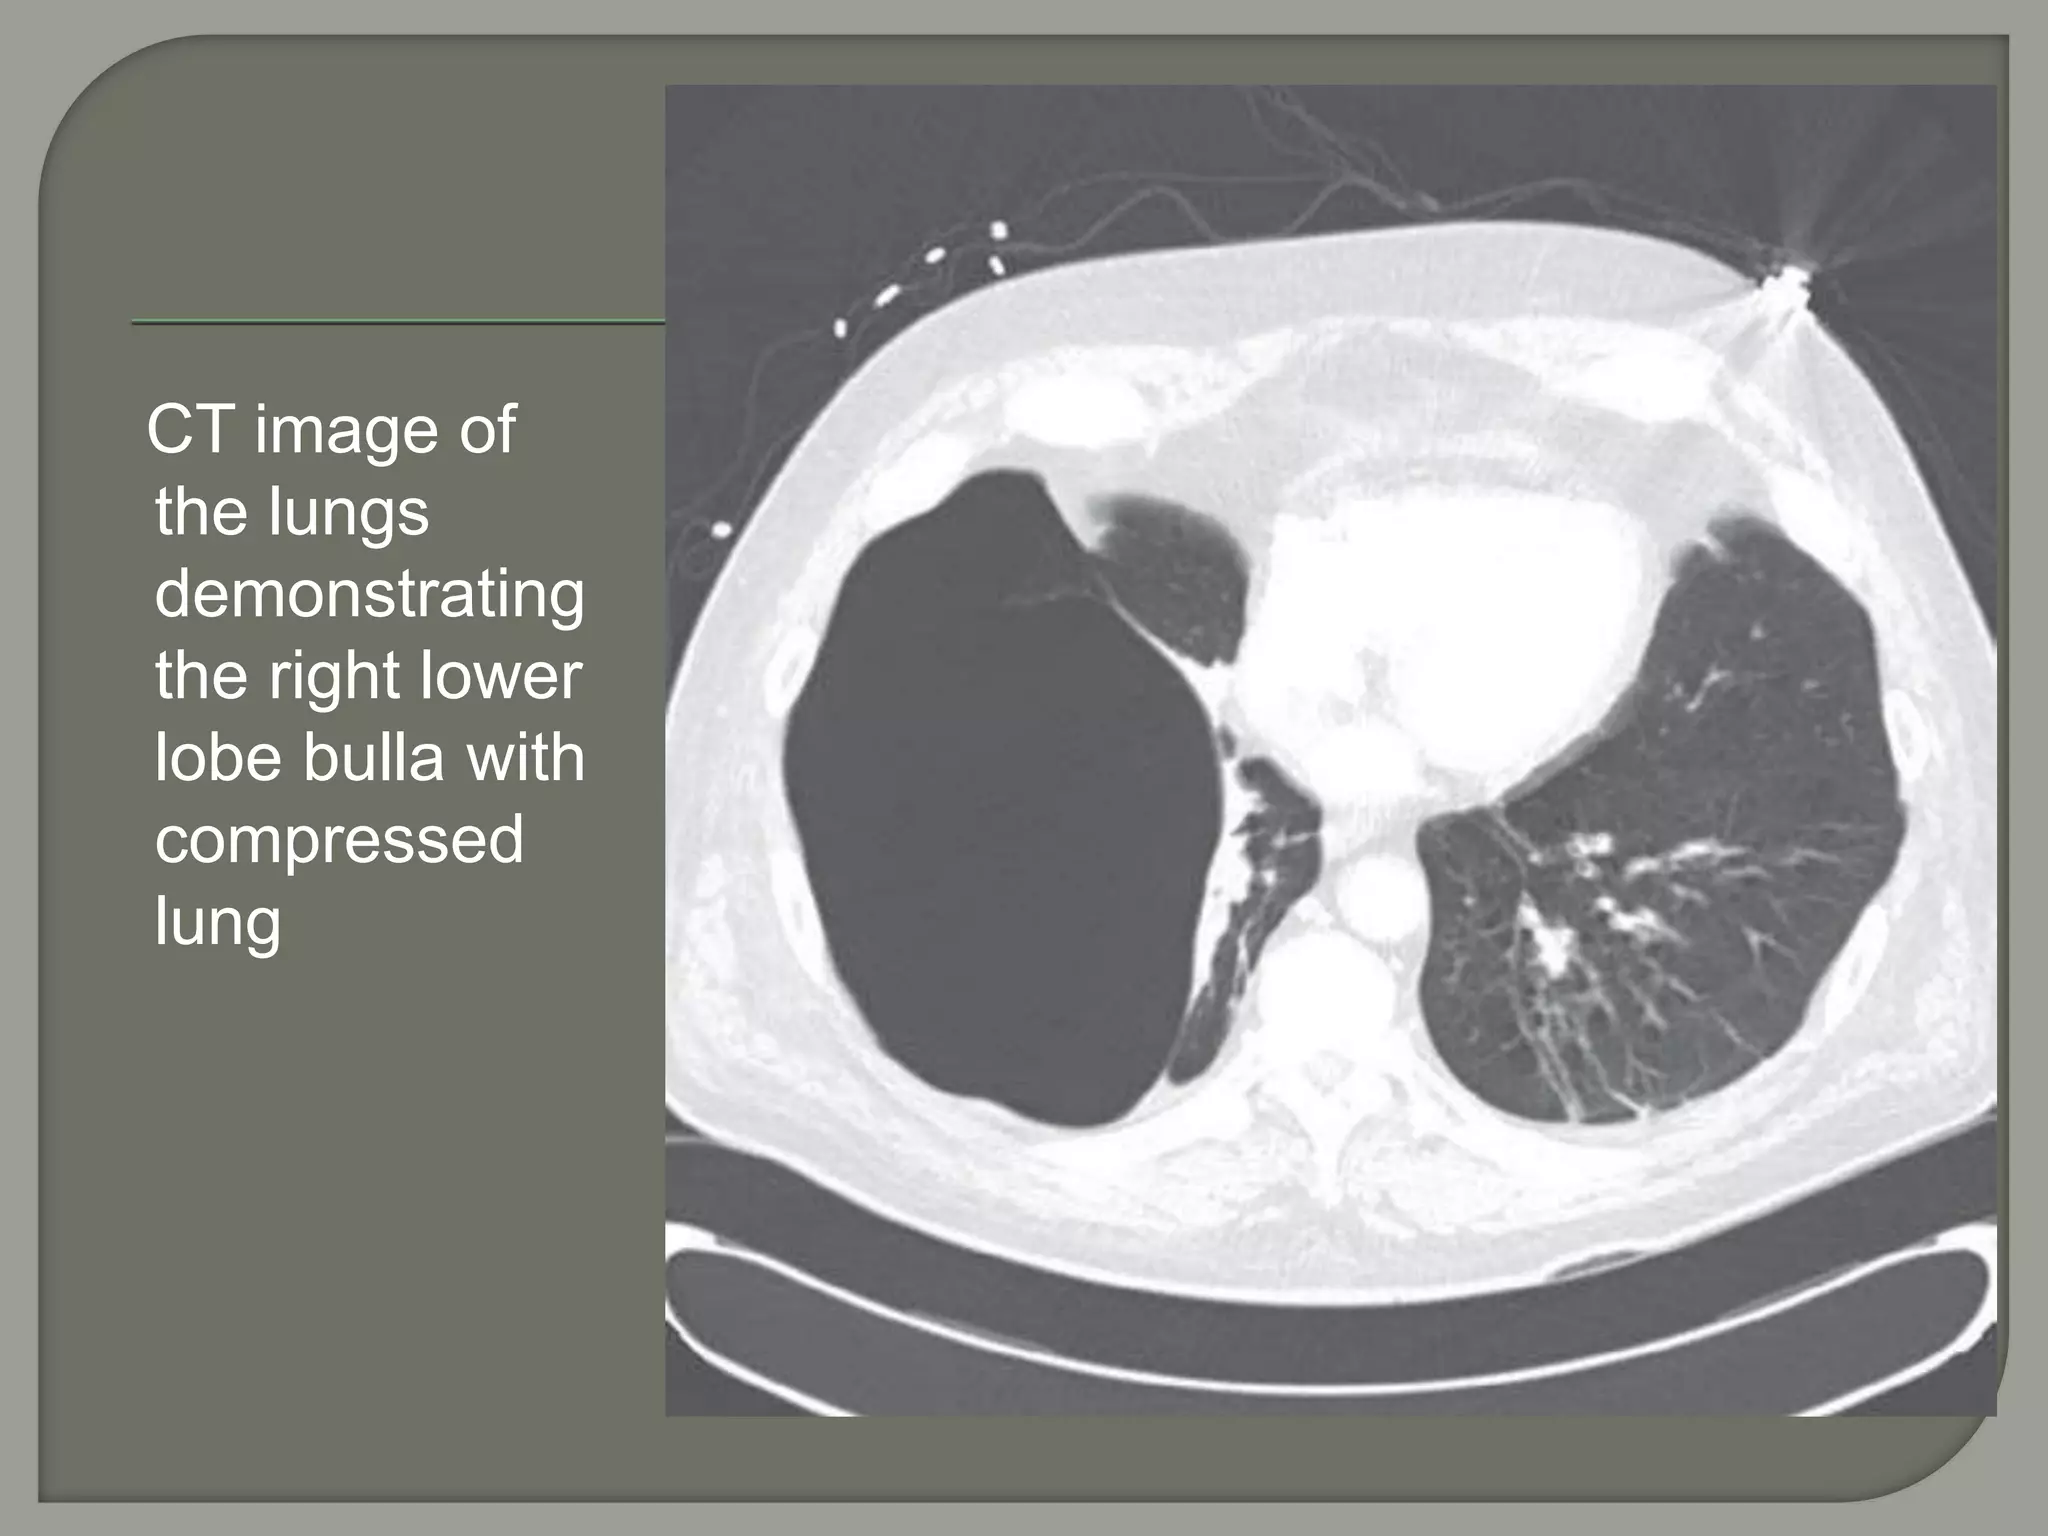

CT image of

the lungs

demonstrating

the right lower

lobe bulla with

compressed

lung

Giant bullae are predominantly located in the

upper lobes and generally subpleural.

However, in patients with

α1-antitrypsin deficiency, bullae are most

commonly located at the lung bases.